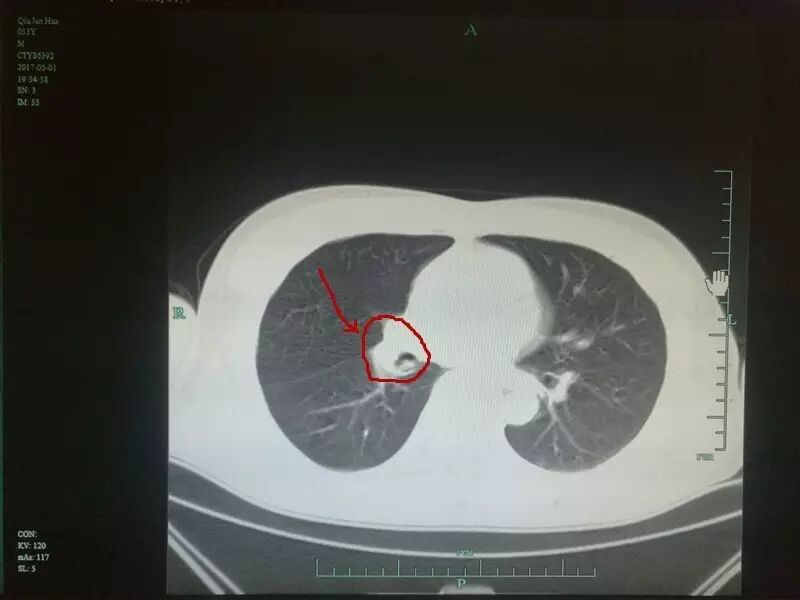

“他(裘先生)的这只虾卡得算比较深的,卡在了右侧肺部中间的支气管位置,不仅中间支气管已经被堵牢,差一点就堵牢主气管了,一旦主气管堵牢那是有窒息的风险的。”浙大一院嵊州分院呼吸内科主任丁勇敏主任医师说,他清楚地记得裘先生就诊时的样子。

急诊入院后,首诊医生发现裘先生的支气管里确实有一异物,形似一只虾。

(裘先生肺里的虾 院方供图)

考虑裘先生吞进去的是一整只,还没有剥壳,且带虾刺的虾。若虾刺随时扎破气管壁或血管,患者很可能会发生大出血,为此,首诊医生找到了丁勇敏主任。